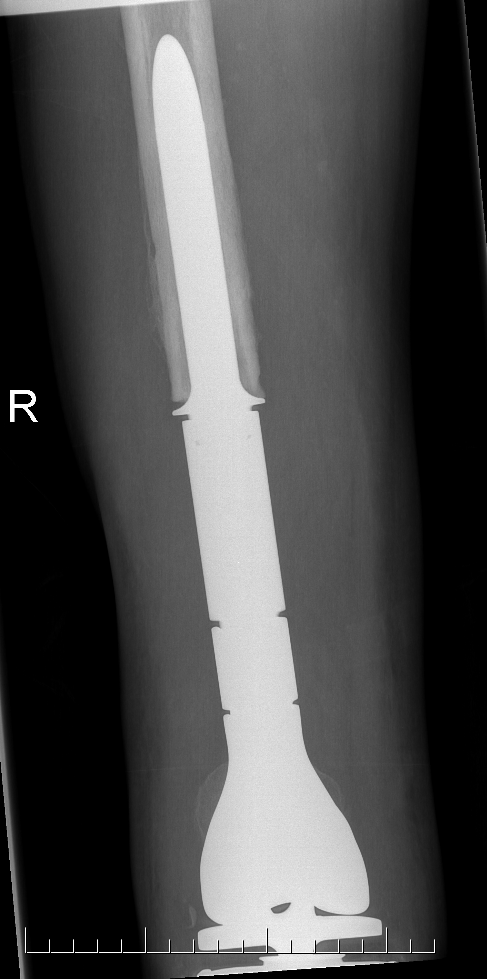

Post proximal tibial osteosarcoma resection